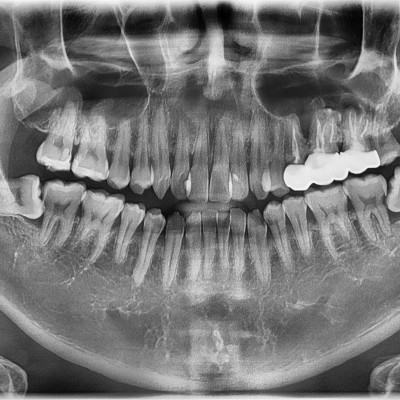

#48 사랑니 발치 N새글 #48 사랑니 발치 구강 외과 전문의가 당일 발치했습니다. -----------------------------..